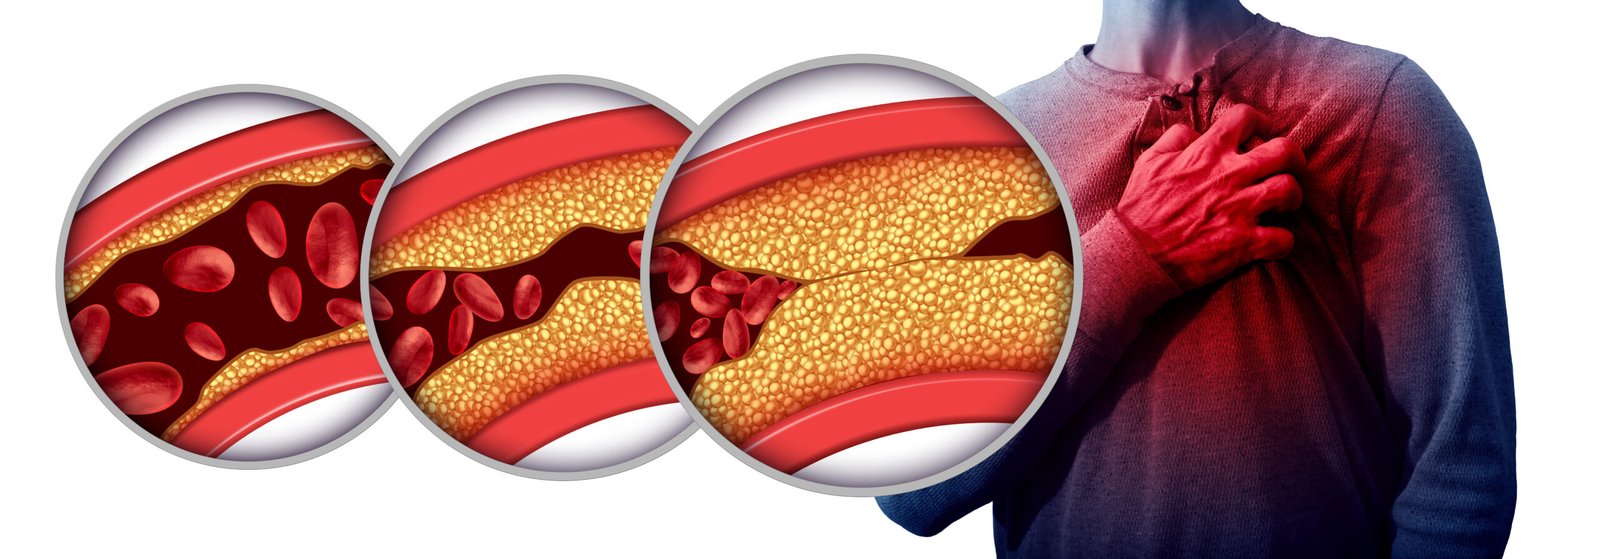

- Coronary Artery Disease: Coronary artery disease (CAD) is a condition where plaque buildup inside the coronary arteries narrows them, reducing blood flow to the heart muscle. This can lead to angina (chest pain or discomfort) and increase the risk of heart attack if a coronary artery becomes completely blocked.

- High Cholesterol: High cholesterol refers to elevated levels of cholesterol and other fats (lipids) in the blood. Excess cholesterol can contribute to the formation of plaque in the arteries (atherosclerosis), narrowing them and reducing blood flow. This increases the risk of coronary artery disease, heart attack, and stroke.